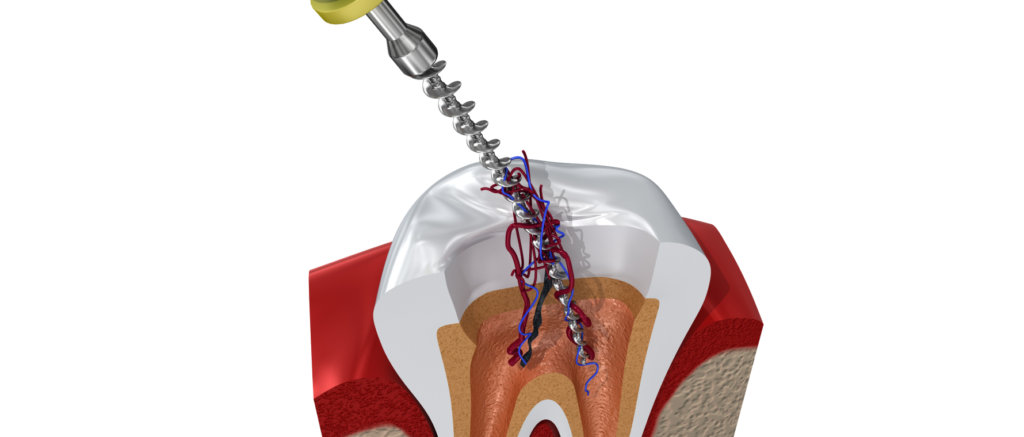

Le traitement des racines suit plusieurs étapes précises. D’abord, la dent est anesthésiée. Ensuite, elle est isolée pour éviter toute contamination. Puis, la pulpe infectée est retirée.

Les canaux sont nettoyés et désinfectés. Enfin, ils sont obturés avec un matériau étanche. Ainsi, les bactéries ne peuvent plus s’y développer.